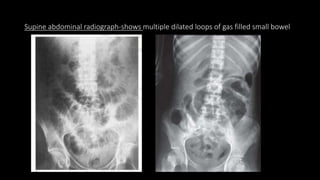

Supine abdominal radiograph-shows multiple dilated loops of gas filled small bowel

On Plain films

• Dilated gas filled loops of small bowel.

• Multiple fluid level

• Dilated small bowel almost completely filled with fluid with small bubbles of gas

trapped in rows between the valvulae conniventes-”string of beads” sign.